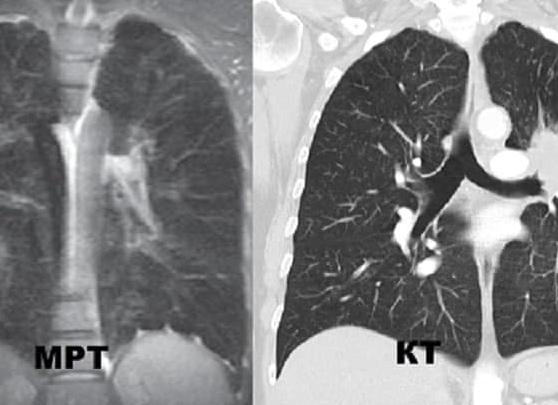

Что лучше МРТ или КТ лёгких и бронхов

Чтобы ответить на вопрос, какой метод диагностики лучше использовать – магнитно-резонансную томографию (МРТ) или компьютерную томографию (КТ), нужно понимать суть этих методов, учитывать скорость проведения, противопоказания к процедуре, и то, что нужно врачу выяснить по результатам обследования. В любом случае только специалист, опираясь на общие показатели здоровья пациента, состояния дыхательной системы, лёгких, может правильно подсказать, в чём отличия, что лучше — МРТ или КТ лёгких и бронхов.

Выясняя, что лучше применять, МРТ или КТ легких, нужно иметь в виду следующее: прежде всего нужно отметить, что КТ и МРТ легких и бронхов зиждутся на совершенно различных физических параметрах и явлениях. Аппаратура устроена по-разному, использует разные данные.

• КТ представляет собой рентгеновские лучи, цель которых – предоставить максимум информации о физическом состоянии исследуемых веществ. ее чаще применяют при поражении грудной клетки, таза, живота или основания черепа.

• МРТ основано на действии стабильных, пульсирующих магнитных полей, радиочастотном излучении, что предоставляют сведения о том, как распределяются протоны (то есть атомы водорода). Таким образом, это исследование выдает сведения не о физическом, а о химическом построении и состоянии тканей. Именно потому лучше различаются мягкие ткани, а вот костные структуры резонанса совсем не дают.

Если врач решает использовать КТ, то он будет видеть сами ткани, получит возможность изучить их рентгеновскую плотность, меняющуюся по мере развития болезни. Если же задействуется МРТ, специалист вынужден оценивать получаемые изображения только визуальным способом. Частенько эти методики равноценны и взаимозаменяемы, или могут использоваться параллельно. Но есть ряд случаев, когда более предпочтительна одна или другая. МРТ предпочтительнее в следующих случаях: